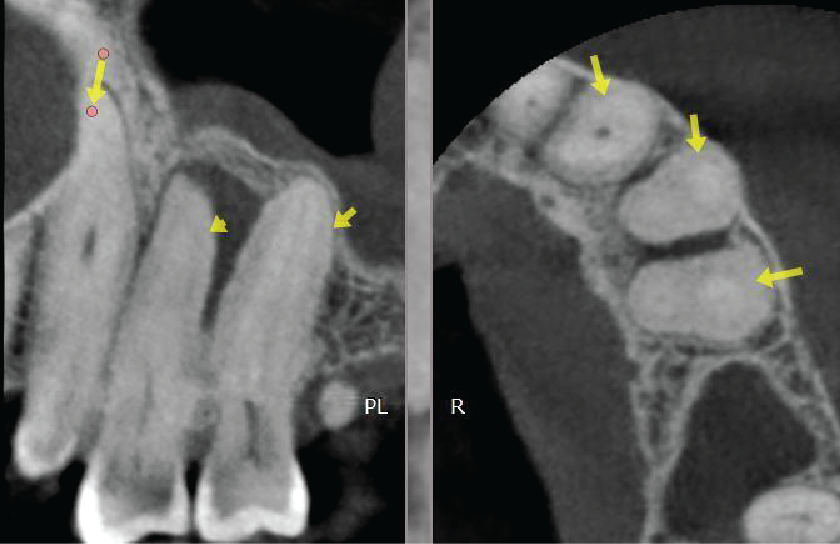

The UL4 has two roots which are practically fused due to hypercementosis. The buccal root is straight. The palatal root has a slight buccal curve. The apical half of both roots is not visible (possibly obliterated). Image 2

Between the UL4 and UL5 there is a well-defined radiolucency measuring approximately 6mm diameter. The lesion envelops the UL4 apex and abuts the apical half of the UL5 root. The genesis of the radiolucency is not of obvious endodontic origin since both teeth are unrestored and the location is not typically centred around the apex. If the teeth are vital, suggested tentative diagnosis are odontogenic cyst such as lateral periodontal cyst or fibro-osseous origin. Image 4